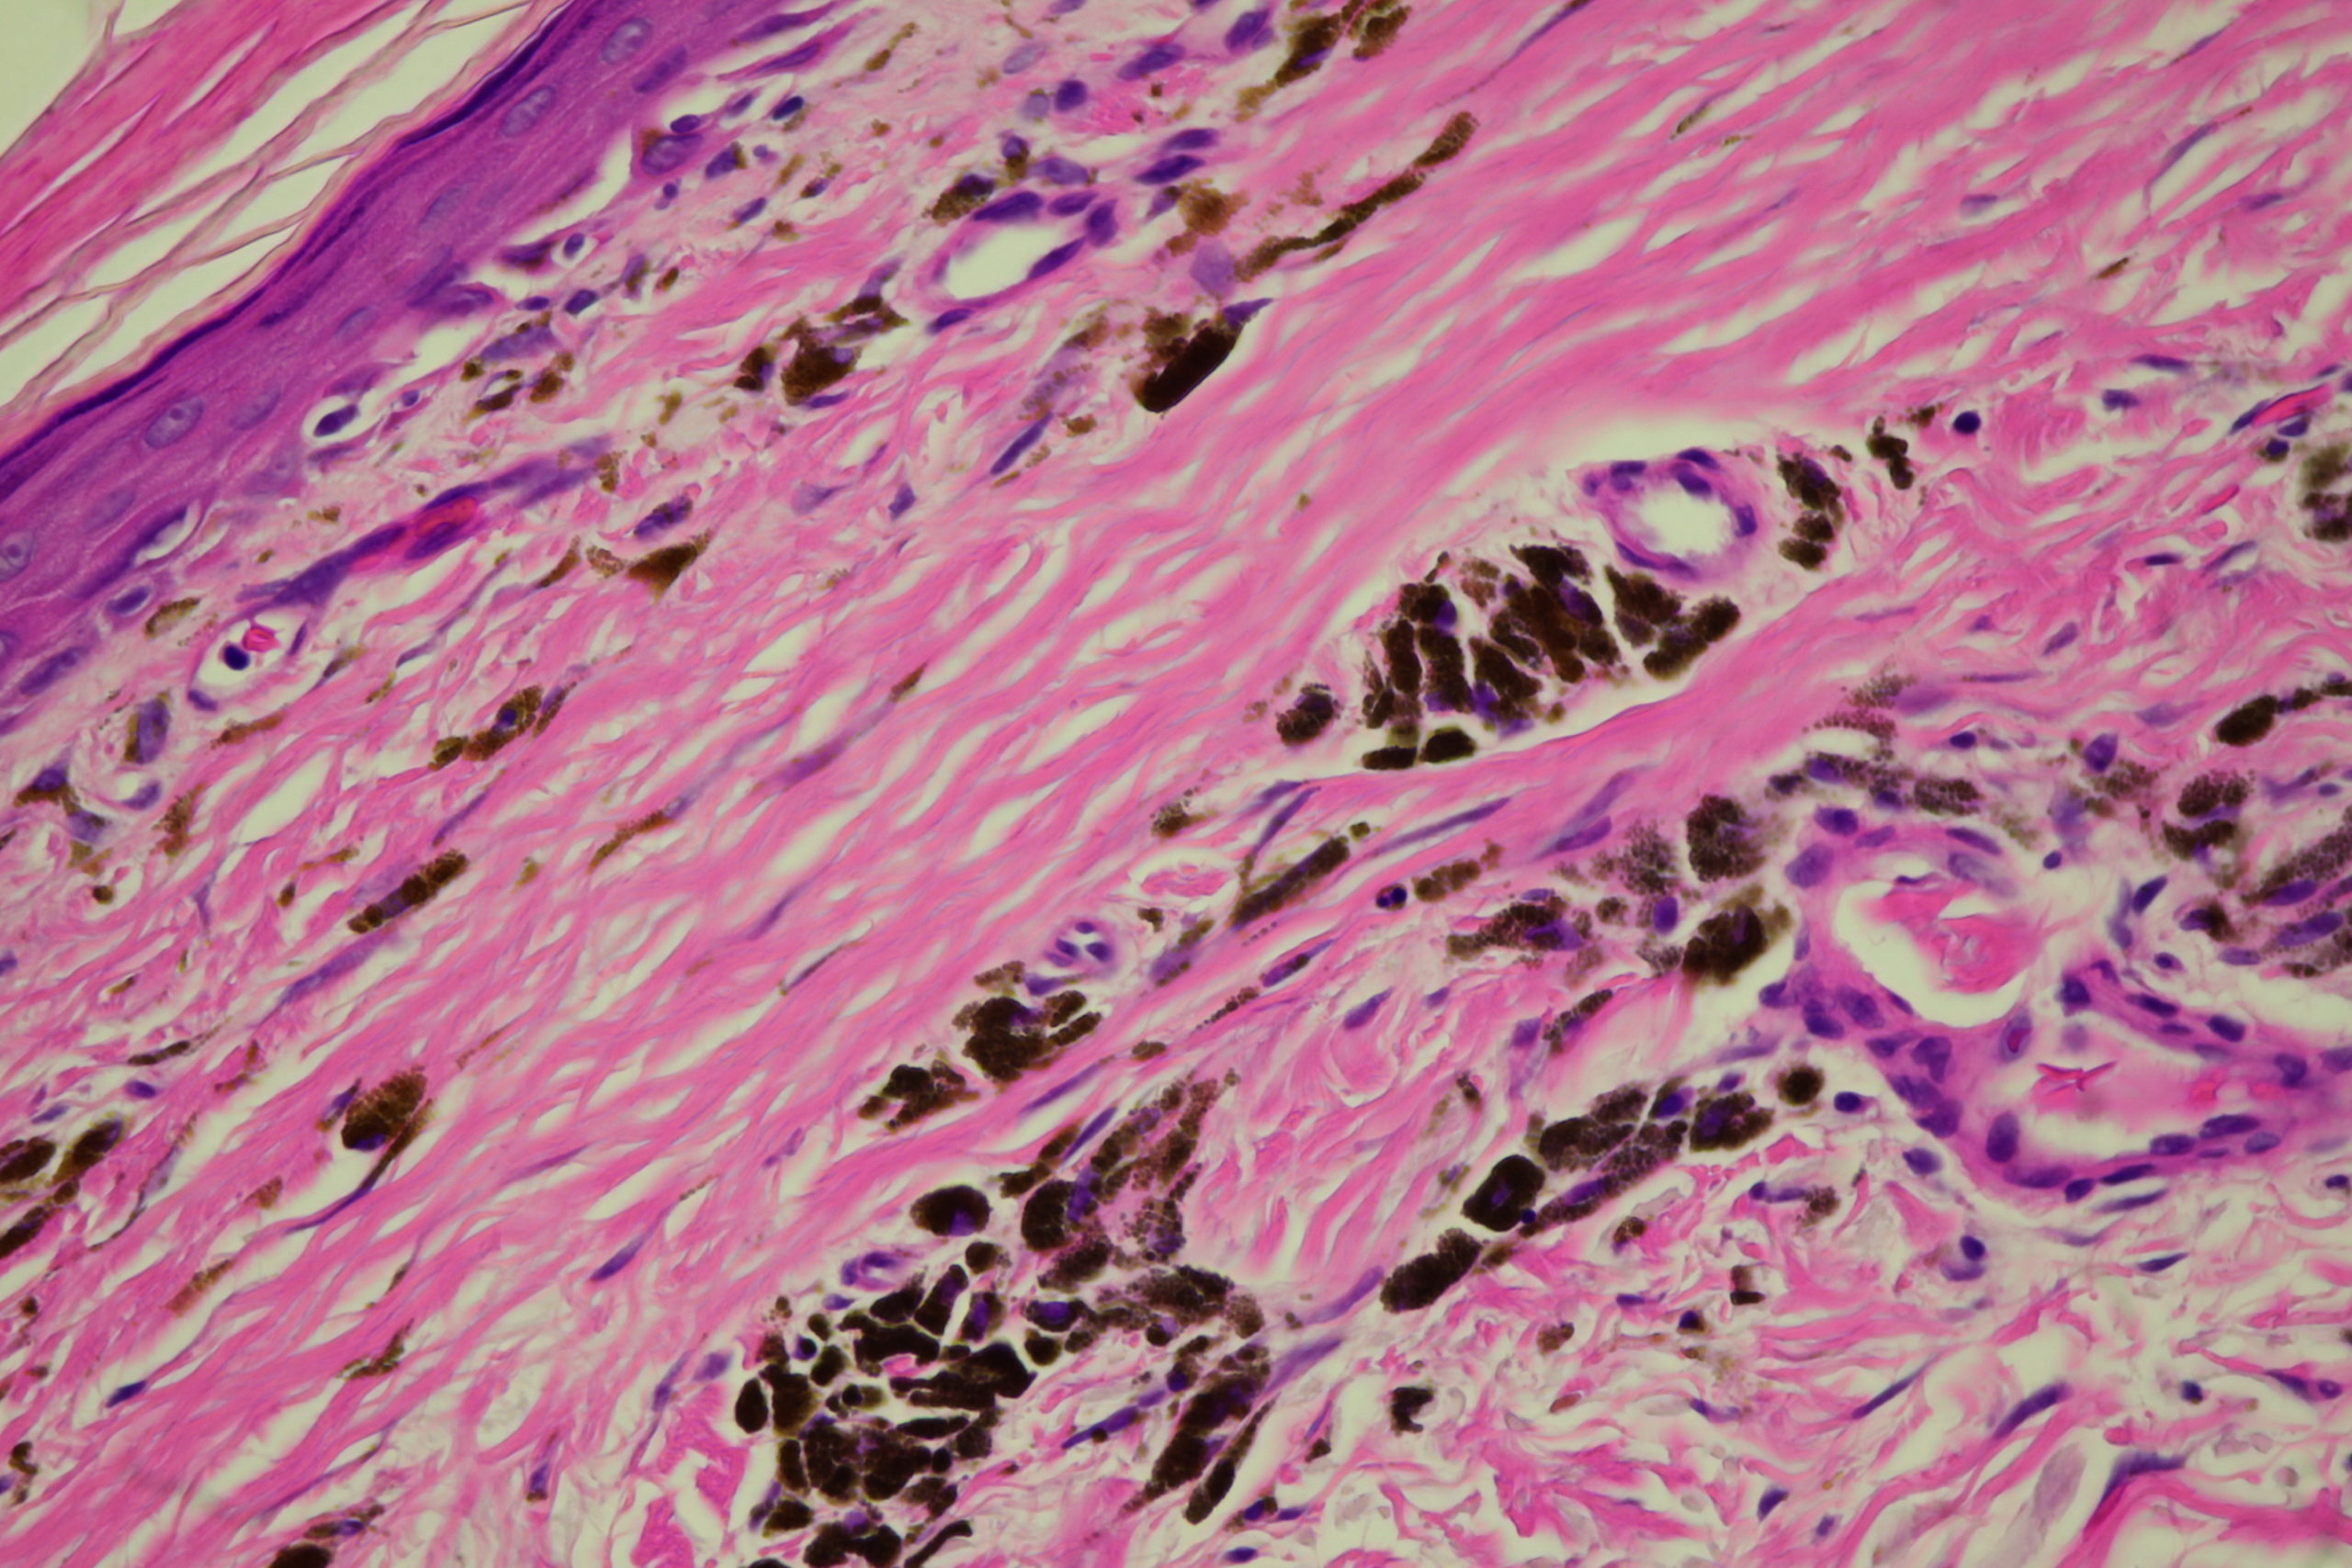

Diagnosis: Post Inflammatory Hyperpigmentation

Description: Note the perilesional hypopigmentation

These lesions arose after he went on Check Point inhibitor for metastatic melanoma. Note the perilesional hypopigmentation as well as the post inflammatory hyperpigmentation which was all that was left of his melanoma metastases. These had been stable for the last 9 months with no evidence in PET scans of melanoma elsewhere. This rteally shows the effectiveness of these immune stimulating drugs in metastatic melanoma.